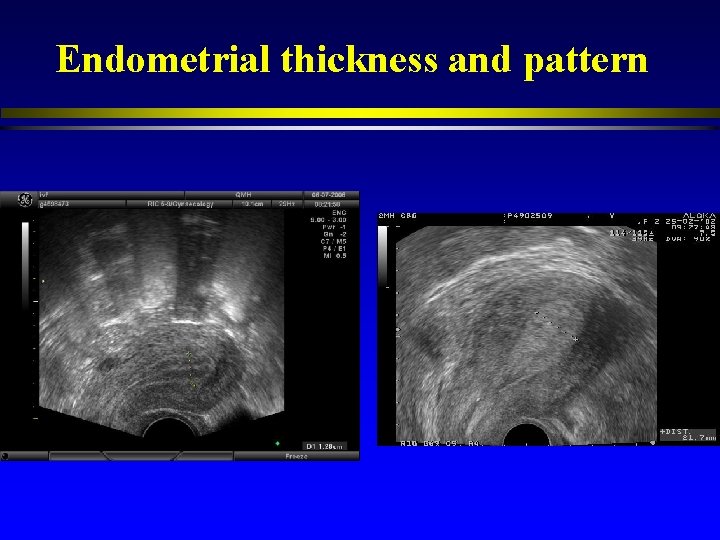

Endometrial thickness and pattern

Endometrial thickness and pattern l Endometrial thickness: cut-off values between 6 -10 mm to discriminate between pregnant and non-pregnant cycles l Low positive predictive value and specificity in the prediction of the IVF outcome (Turnbull et al. , 1995; Friedler et al. , 1996).